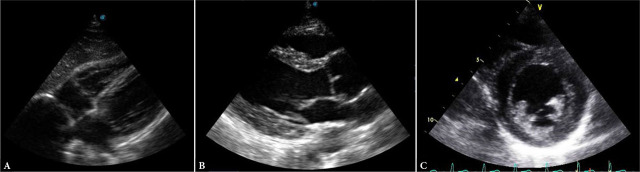

Results: POCUS-CRAFT represents five components of trauma patient evaluation. C (Cranium): Transcranial Doppler or transorbital ultrasound to assess for elevated intracranial pressure; R (Respiratory): Evaluation of the chest for pneumothorax and pleural hematoma; A (Abdomen): Evaluation of the peritoneal and pelvic cavity for free fluid; F (Cardiac Function): Diagnosis of pericardial tamponade and assessment of left ventricular systolic function; T (Trauma Integration): Integration of ultrasound findings with a complete physical examination of the trauma patient, with emphasis on the clinical context.

Abstract Image